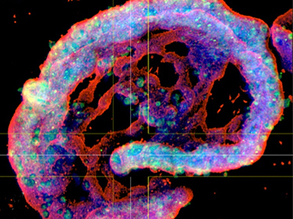

Vessel Makers